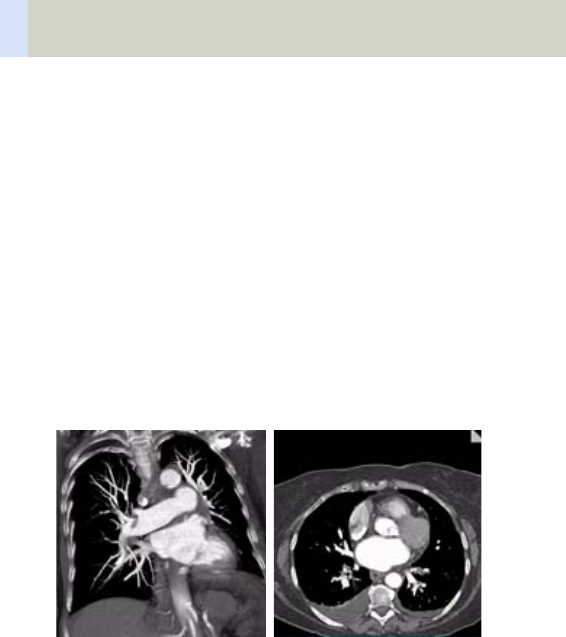

- ThorAngioRoutine/

ThorAngioRoutine06s 380

- ThorAngioVol 384

- Embolism/

Embolism06s 394

- HeadTraumaSeq 432